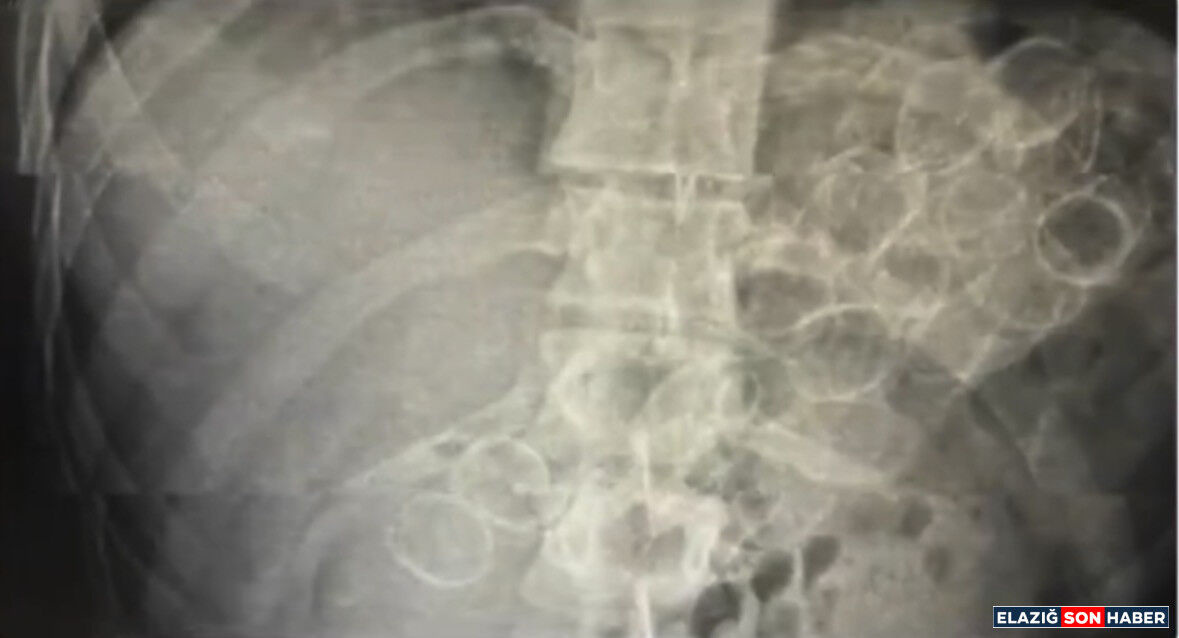

Bingöl İl Emniyet Müdürlüğü Narkotik Suçlarla Mücadele Şube Müdürlüğü ekiplerince yürütülen çalışmalar neticesinde, "Uyuşturucu veya Uyarıcı Madde Ticareti" suçu kapsamında 3 şahsın "yutma ve tıkma" yöntemiyle mide ve bağırsaklarında yüklü miktarda uyuşturucu madde taşıyarak kente getirdiği belirlendi. Ekipler tarafından yakalanan şüphelilerin hastanede yapılan tedavileri sonucunda, toplam 75 kapsül halinde 775 gram metamfetamin maddesi ele geçirildi.